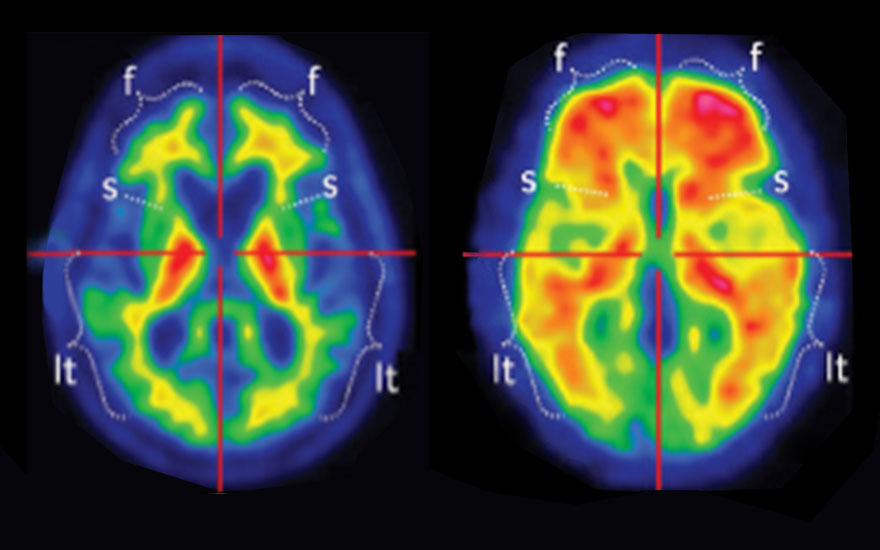

A la izquierda, imagen PET de paciente sano. A la derecha, de enfermo de Alzheimer donde se aprecia acumulación de proteína beta-amiloide.

, jefe del servicio de Neurología del Hospital Universitario Quirónsalud Madrid y del Complejo Hospitalario Ruber Juan Bravo. "En la actualidad los tratamientos contra el Alzheimer no son todo lo efectivos que desearíamos porque comenzamos a aplicarlos cuando la enfermedad empieza a mostrar síntomas. En esos momentos ya es tarde porque ya hay depósitos de la proteína beta-amiloide en el cerebro. Queremos detectar a las personas que portan la variedad del gen de la apolipoproteína A4 en su forma homocigótica por su alto riesgo de desarrollar la enfermedad y proponerles la participación en un ensayo clínico de fármacos preventivos que tratan de eliminar las placas de beta-amiloide". Asimismo, a los que porten esta variedad del gen en su forma heterocigótica se les realizará un PET cerebral para calcular su riesgo de padecer enfermedad de Alzheimer.